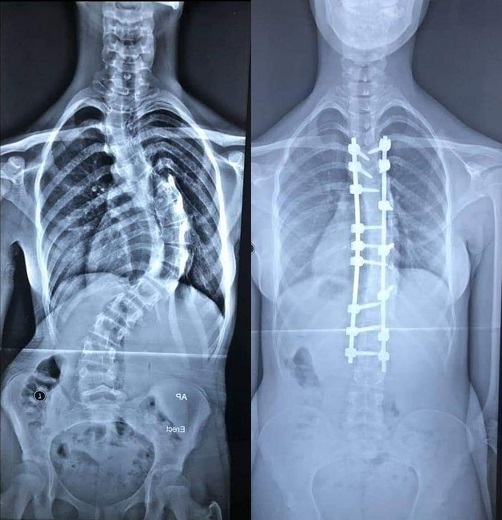

اعلن فريق طبي في مستشفى الكفيل التخصصي بكربلاء نجاحه بمعالجة مريضة كربلائية بعمر الـ(16) عام تعاني من تحدب شديد في العمود الفقري.

وقال الطبيب السوري والمعالج بالمستشفى الدكتور وائل قاسم، اختصاصي جراحة الجملة العصبية، في حديث صحفي، ان فريق طبي برئاستنا نجح بإجراء عملية نوعية لمريضة كربلائية تبلغ من العمر (16) عام تعاني من تحدب شديد في العمود الفقري وغير قادرة على الوقوف باستقامة مثل الاشخاص الاعتياديين.

وبين قاسم، بعد دراسة حالتها الصحية ادخلت الى صالة العملية واجرينا لها عملية استغرقت (7) ساعات تم خلالها تعديل الانحراف باستخدام تثبيت الفقرات وقطع جزء من العمود الفقري لأجراء التعديل.